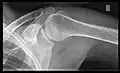

X-ray

Projectional radiography views of the shoulder include:

- AP-projection 40° posterior oblique after Grashey

The body has to be rotated about 30 to 45 degrees towards the shoulder to be imaged, and the standing or sitting patient lets the arm hang. This method reveals the joint gap and the vertical alignment towards the socket.[26]

- Transaxillary projection

The arm should be abducted 80 to 100 degrees. This method reveals:[26]

- The horizontal alignment of the humerus head in respect to the socket and the lateral clavicle in respect to the acromion

- Lesions of the anterior and posterior socket border, or of the tuberculum minus

- The eventual non-closure of the acromial apophysis

- The coraco-humeral interval

- Y-projection

The lateral contour of the shoulder should be positioned in front of the film in a way that the longitudinal axis of the scapula continues parallel to the path of the rays. This method reveals:[26]

- The horizontal centralization of the humerus head and socket

- The osseous margins of the coraco-acromial arch and hence the supraspinatus outlet canal

- The shape of the acromion

This projection has a low tolerance for errors and, accordingly, needs proper execution.[26] The Y-projection can be traced back to Wijnblath’s 1933 published cavitas-en-face projection.[27]

-

CR. shoulay film. -